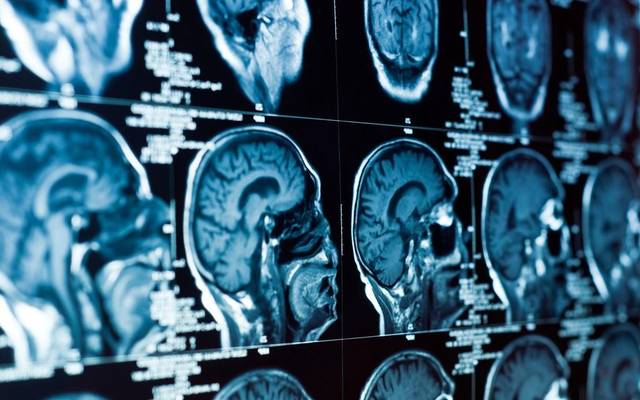

我们平时所说的“中风”是我国传统中医的说法。在疾病分类上,称为脑卒中。分为出血性脑卒中与缺血性脑卒中两种类型。也就是我们平时所说的脑出血与脑梗死。虽然看起来这两种疾病好像截然相反,但实际上它们有共同的病因基础,最主要的因素就是高血压与脑动脉硬化。所以预防中风,我们就要从病因上入手。